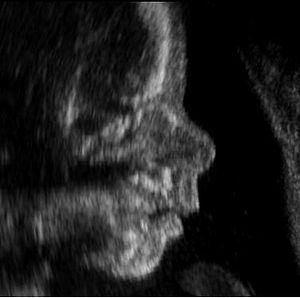

Las ecografias estructurales son aquellas en las cuales se realiza una revision detallada de la anatomia fetal. Hay una evaluacion organo por organo del feto y con esta revision sistematica se puede descartar anomalias cromosomicas y anomalias en la formacion de alguno de los organos del bebe.

1. Entre las 11-14 semanas. Mas recientemente se recomienda que a las 12 semanas, ya que se puede ver mejor la anatomia fetal y la deteccion es mayor.

2. Entre las 18 semanas a las 24semanas. En nuestro Centro preferimos hacerlo alrededor de las 22 semanas.